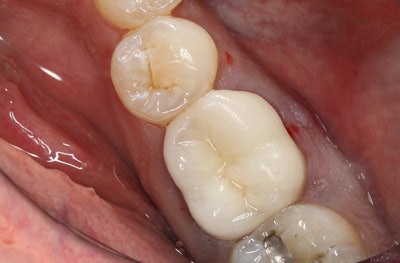

The patient in this case presented with a nonrestorable, root canal-treated mandibular molar tooth (figures 1-3). After patient consultation, it was decided that the tooth would be extracted and grafted in preparation for a dental implant.

Since the roots were divergent and it was a mandibular molar tooth where the bone is more dense, the treatment plan included the following:

- The crown would be removed.

- The tooth would then be sectioned and extracted as individual roots.

- The site would then be grafted with a simple technique in preparation for a future dental implant.